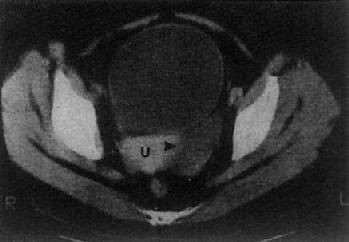

子宫体在CT上易于识别,显示为横置的密度较高的梭形影像,CT值40~80Hu,宫体中央密度可略低。子宫大小受年龄和生理状态的影响,一般成人前后径为1.5~3cm,左右径为3~5cm,老年人子宫较小。膀胱充盈程度也影响子宫的大小。子宫前方为膀胱,呈液性低密度;后方为直肠,内常有气体。膀胱、子宫、直肠之间常有肠袢存在。宫颈在宫体下方层面,呈卵圆形软组织影。卵巢位于子宫侧壁和臼内壁之间,正常大小时CT常不见。增强扫描,子宫密度均匀增加,膀胱内造影剂为高密度,盆腔内血管输尿管显示为高密度,易于识别(图4-5-5)。

图4-5-5 女性盆腔正常CT表现

子宫呈横行的梭形软组织影(↓),其前方为膀胱(B)

其后方、骶骨之前为直肠(R)